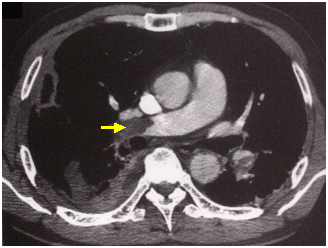

胸部の造影エックス線CTは、特にエックス線CTの進歩により肺動脈末梢の小さな血栓まで正確に診断されるようになり、現在では専ら造影エックス線CTにより診断される(図1)。

図1 肺血栓塞栓症。胸部造影エックス線CT。右肺動脈に閉塞が認められる(矢印)。(原論文3より引用)